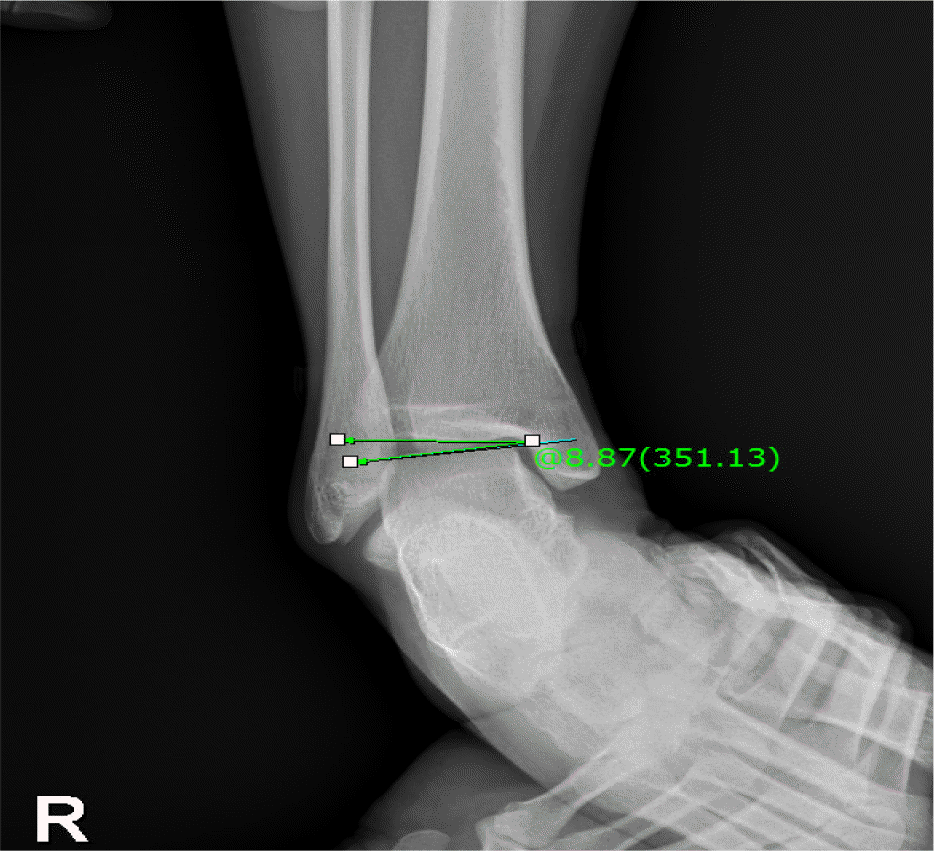

Comparison of ankle range of motion, functional ability and talar tilta

| Variables | FDG (n=8) | NCG (n=10) | t | df | Pb |

|---|---|---|---|---|---|

| Range of motion | |||||

| PF, ○ | 82.75±5.52 | 92.60±8.69 | –2.778 | 16 | 0.013 |

| DF, ○ | 19.37±6.20 | 21.30±8.98 | –0.514 | 16 | 0.614 |

| Functional ability | |||||

| Balance test, s∗ | 32.37±26.75 | 38.50±16.47 | –0.598 | 16 | 0.558 |

| Side step test, times/20 s | 16.12±1.12 | 16.40±1.17 | –0.503 | 16 | 0.622 |

| Talar tilt, ○ | 6.57±2.95 | 3.70±2.42 | 2.266 | 16 | 0.038 |